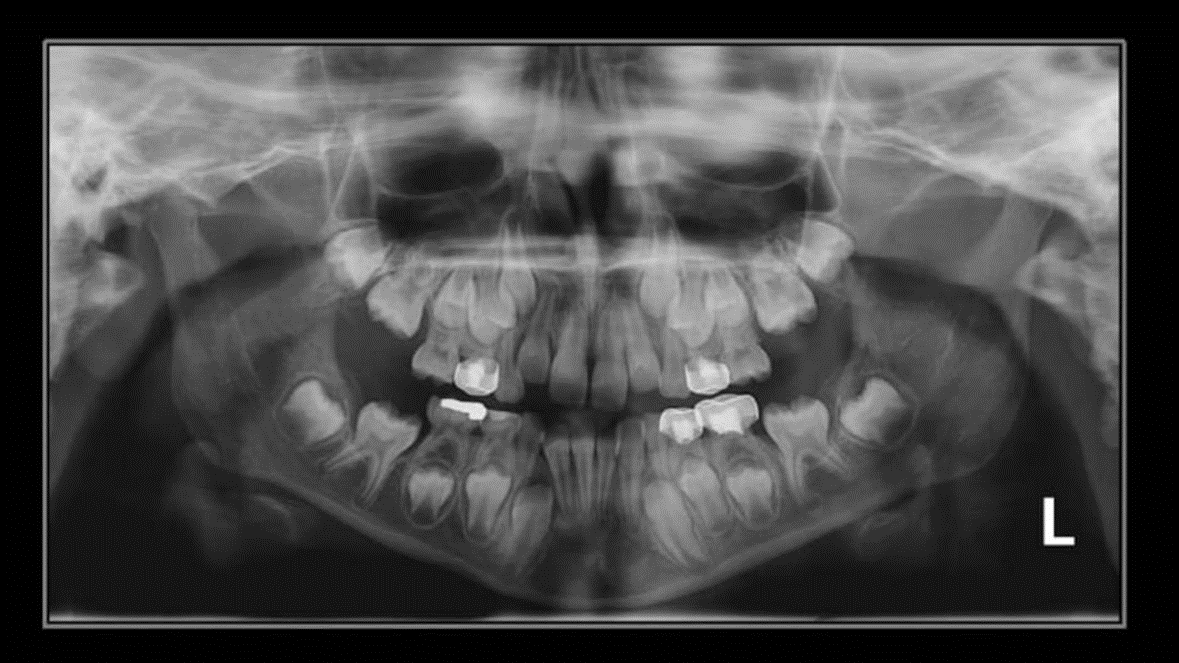

2. How old is the patient with the following X ray?